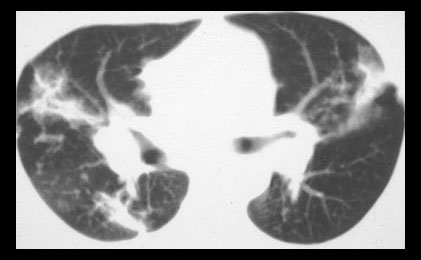

Computed tomography in Stage 4 sarcoidosis shows broad bands of fibrosis in the upper lobes. |